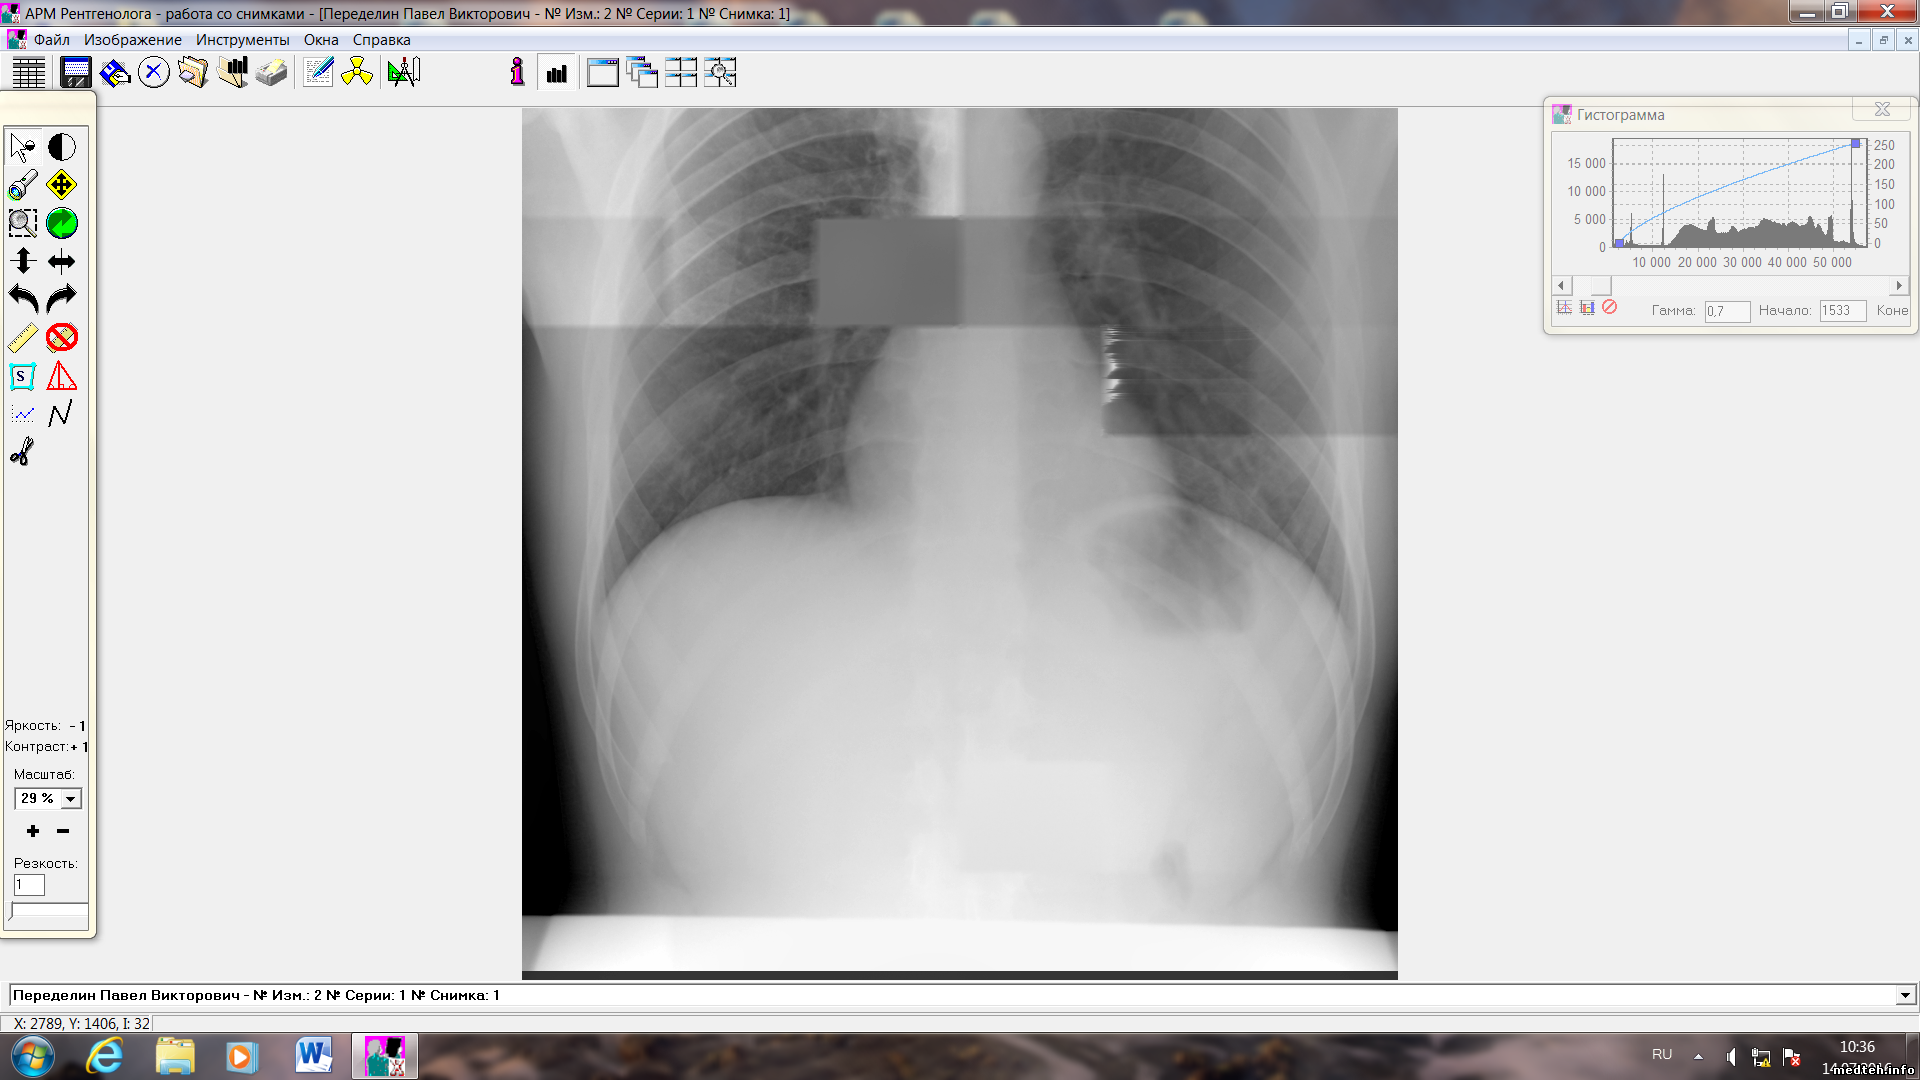

Российская Федерация

На базе палатника АРА и украинской камеры Альфа-Р-4000 собран флюрограф. Снимок прикреплен. Может у кого есть какие мысли? Подскажите. Может у кого нибудь документация. Спасибо.

Все, что там написано 1:1 относится и к Вашему приемнику. На Вашем снимке четко видно, что сдохла 9-я камера. Что конкретно в ней - нужно смотреть. Чаще выходит из строя верхняя платка (СГК).